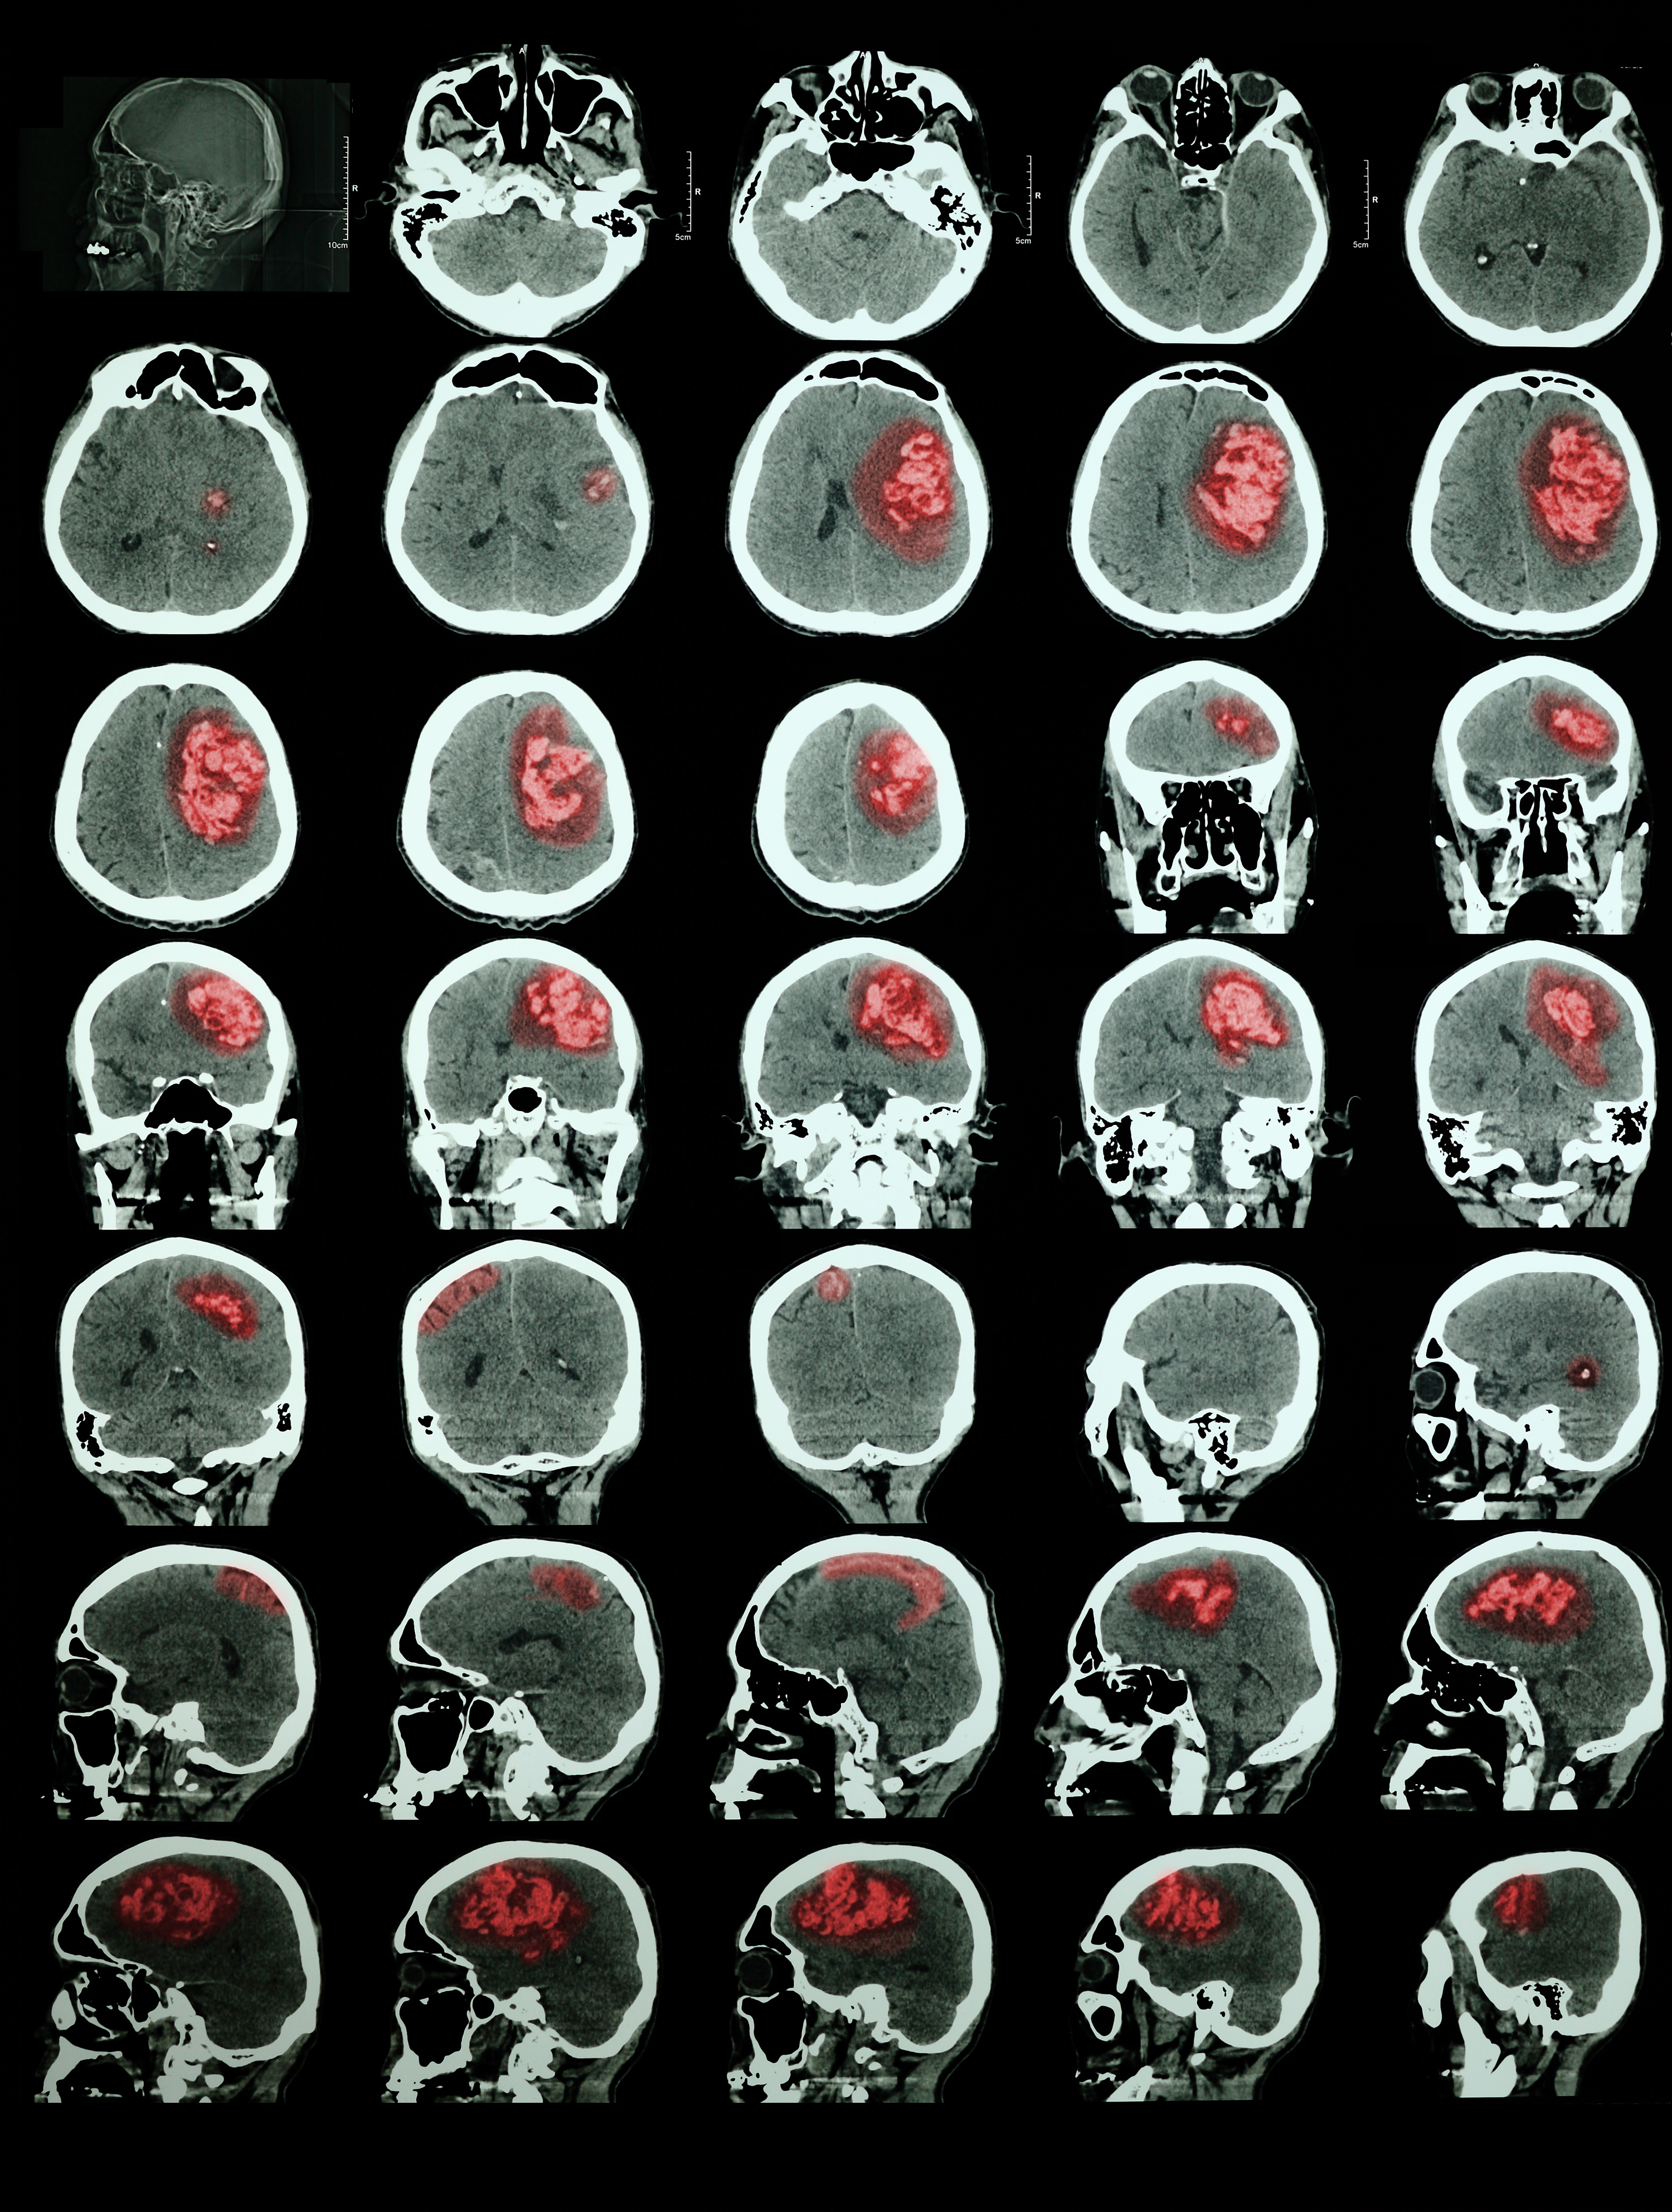

Traumatic brain injuries are classified as mild, moderate or severe. Even so-called “mild closed head injuries” can cause deficits in thinking skills, emotional and behavioral functions, as well as physical abilities.

• Physical problems include fatigue, headaches, nausea, problems with balance or motor skills, loss of coordination, sensory losses, sensitivity to light or sound, sleep disturbance, coma, hemorrhage, and stroke.